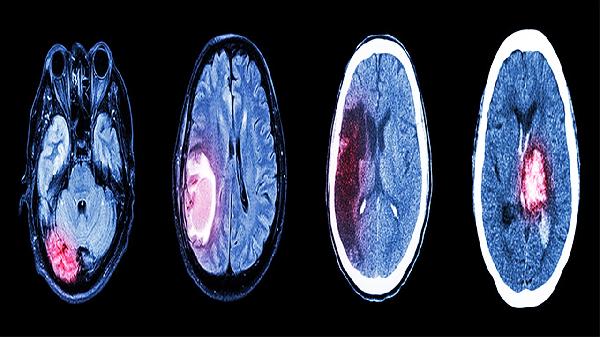

颅脑损伤可能导致脑水肿、颅内感染、癫痫、脑积水和植物状态等并发症。颅脑损伤后需密切监测生命体征,及时干预以降低并发症风险。

脑水肿是颅脑损伤后常见的并发症,主要表现为头痛、恶心呕吐和意识障碍。脑水肿可能与脑血管通透性增加、血脑屏障破坏等因素有关。治疗时可使用甘露醇注射液、呋塞米片等药物减轻脑水肿,必要时需进行去骨瓣减压术。患者需保持头高位,避免剧烈活动。

脑积水常见于重型颅脑损伤后,主要症状为头痛、步态不稳和认知功能下降。脑积水可能与脑脊液循环通路阻塞有关。轻度脑积水可使用乙酰唑胺片治疗,严重时需行脑室-腹腔分流术。术后需定期复查头颅CT评估分流管功能。